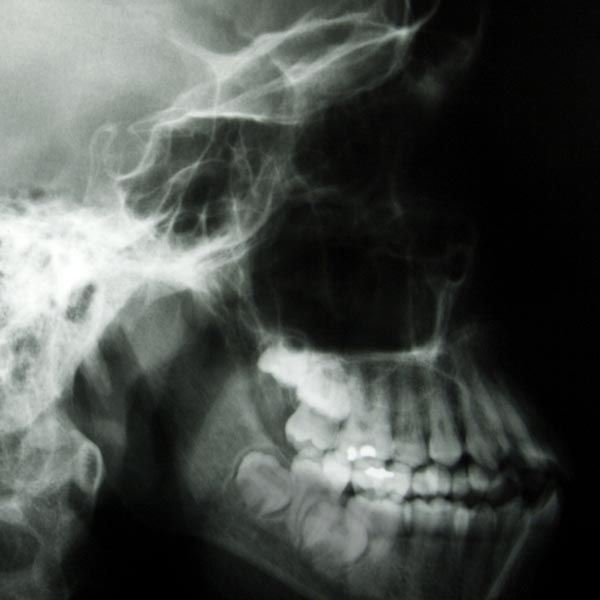

Facial trauma, untreated gum disease, and tooth loss can result in jawbone recession, making it difficult to qualify for dental implants.

Bone grafting is a procedure designed to add volume and density to the jawbone and reestablish your candidacy for implant placement.

One of the roles of tooth roots is to stimulate the jaw, which signals that nutrients are needed in the area. When you lose a tooth, your brain reroutes essential nutrients away from that area of the jaw.

The longer a tooth is missing, the more likely it is that the jaw will begin to atrophy. Over time, this tissue loss can affect the stability of other teeth, cause further tooth loss, and give your face a sunken, aged appearance.

After a certain point, the jaw loses so much tissue that placing implants is no longer an option without first performing a dental bone graft.